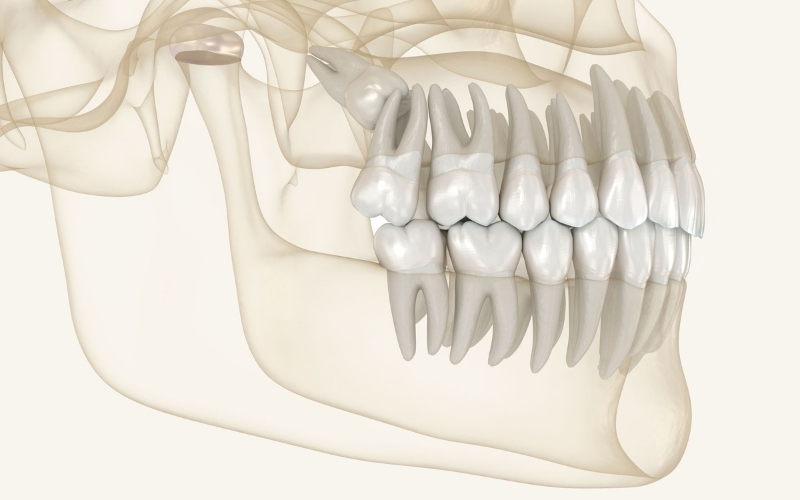

"Nedprioritering af børnene kan mærkes hele livet"

Nuno Vibe Hermann svarer på, hvordan hun vurderer udviklingen og de fremtidige perspektiver for den kommunale tandpleje ud over udvidelsen til de 18-21-årige.